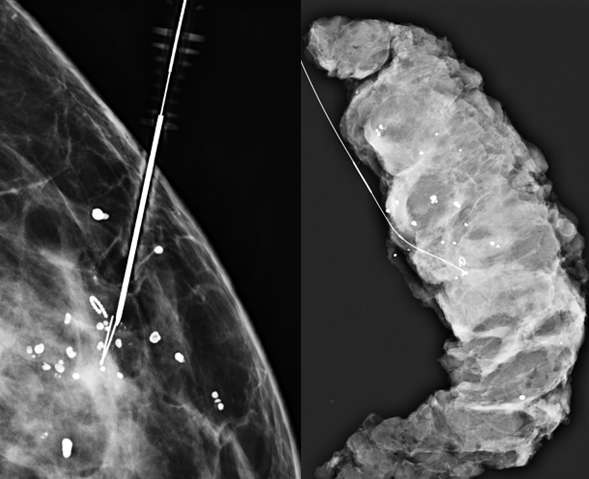

Technologist takes 2D or 3D mammogram with wire(s) in place (Figure 4).

Radiologist evaluates for adequate placement.

At surgery, tissue samples are packaged appropriately and sent for specimen radiography followed by histological analysis.